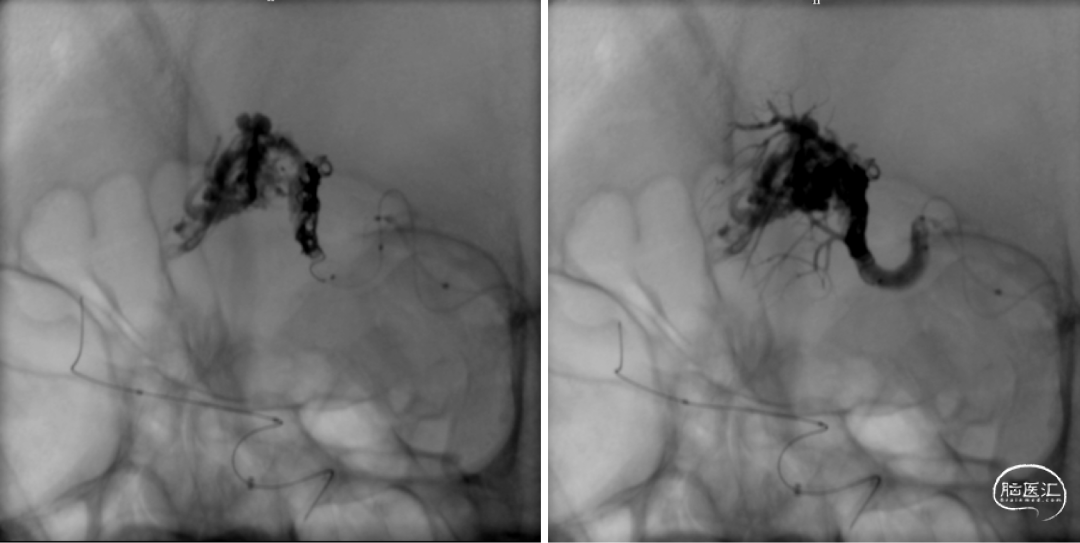

术中:超选外侧豆纹动脉(马拉松塑形),synchro10+0.008塑形,到位,15%gb,时间5min,返流拔管稍粘连。

术中:Enoyv6f双导丝到乙状窦,synchro10将apollo3cm到位;泰杰312、310x2(做塞子);控制收缩压在90以内,动脉内hyperglide4x20充盈(保护),onyx34约0.6ml(约5min),换onyx18弥散差。

术中:即刻造影脑动静脉畸形消失。